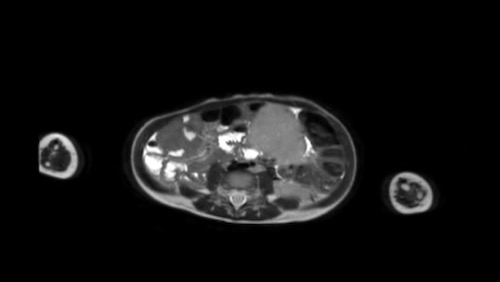

Đây là hình ảnh T1W axial có tiêm gadolinium với kỹ thuật xóa mỡ.

Hình ảnh cho thấy sự bao bọc của các mạch máu.

Lưu ý sự lan rộng của khối u ra phía sau động mạch chủ, đẩy động mạch chủ ra xa cột sống (mũi tên).